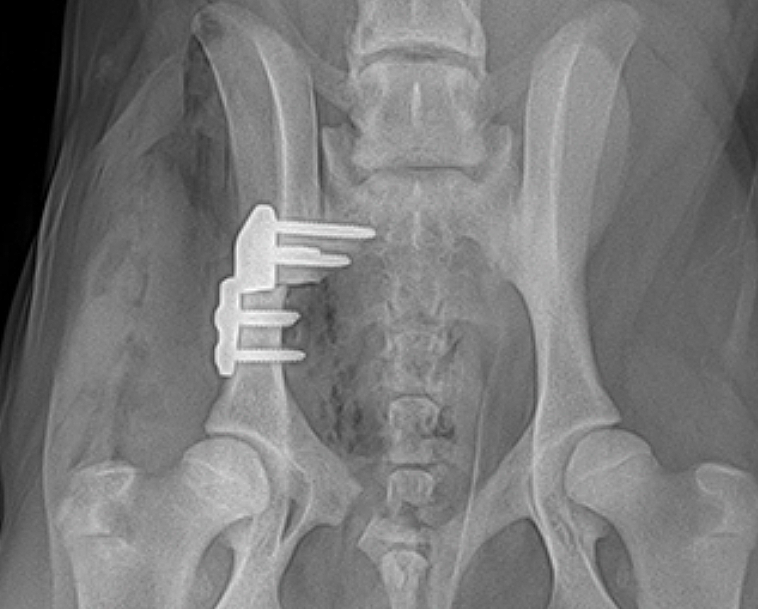

고관절 통증 증상은 조기에 발견하고 치료받는 것이 무엇보다 중요합니다. 고관절 손상이 심하지 않고 통증이 가볍다면 약물치료와 운동치료 등 보존적 치료를 통해 회복할 수 있습니다. 하지만 고관절 손상이 심하고 일상생활에 지장을 줄 만큼의 심한 고관절 통증 증상이 있는 경우라면 괴사된 관절을 제거하고 인공관절을 삽입하는 고관절의 인공관절 치환술을 해야 합니다.